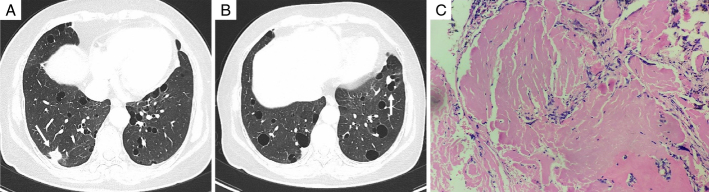

Results: Among the 13 patients, there were 3 males (23.08%) and 10 females (76.92%). Their ages ranged from 37 to 68 years, with a mean age of (57.85±8.40) years and a median age of 59 years. Three (23.08%) patients had cough and sputum, while the others (76.92%) had no clinical symptoms. Before surgery, 6 patients underwent chest CT scans, and NPA changes in size, shape, and density were observed. Six cases (46.15%) were located in the left lung (4 in the upper lobe and 2 in the lower lobe), and 7 cases (53.85%) in the right lung (3 in the upper lobe, 2 in the middle lobe, and 2 in the lower lobe). Seven cases (53.85%) of NPA were round or oval, while 6 cases (46.15%) were irregularly shaped. Out of the NPA cases, 11 (84.62%) were solid nodules with well-defined boundaries, including 2 cases of solid nodules with surrounding calcification. In addition, 2 cases presented as solid nodules with cavities. Ten cases (76.92%) had multiple cystic lesions in the bilateral lungs, in which 7 cases had more than 10 cysts with obvious cyst walls, and 1 case showed a solid nodule on the cyst wall. During the postoperative follow-up, 1 patient experienced an increase in the size of the original nodule and the appearance of new solid nodules. Subsequent surgery revealed mucosal-associated lymphoid tissue lymphoma (MALT). The remaining patients were followed up regularly, and their conditions remained stable.

Conclusions: NPA is more common in middle-aged and elderly people and is more likely to occur in women. Most cases are asymptomatic, and bilateral lungs can be involved. For nodules with multiple pulmonary cysts found by chest CT, the possibility of NPA should be considered, and further histopathologic examination is needed to confirm the diagnosis. Most patients with NPA have a good long-term prognosis after surgical resection, but some patients require further investigation and close follow-up due to underlying causes.